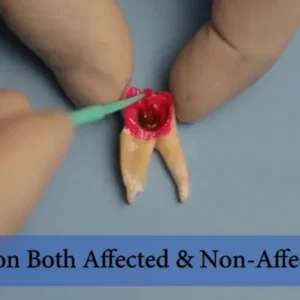

SafeEndo Smart Prep Liquid

SafeEndo EDTA Liquid Solution is a colorless 17% EDTA solution & 0.7% Cetrimide indicated for canal cleaning, smear layer removal, and debridement during chemical & mechanical preparation of root canals. Also to be used as a final rinse solution before the obturation of canals.

- Irrigation and Chelating agent in Root Canal Treatment

- Detection of root canal orifice

- Chemical enlargement of root canals during preparation for filling